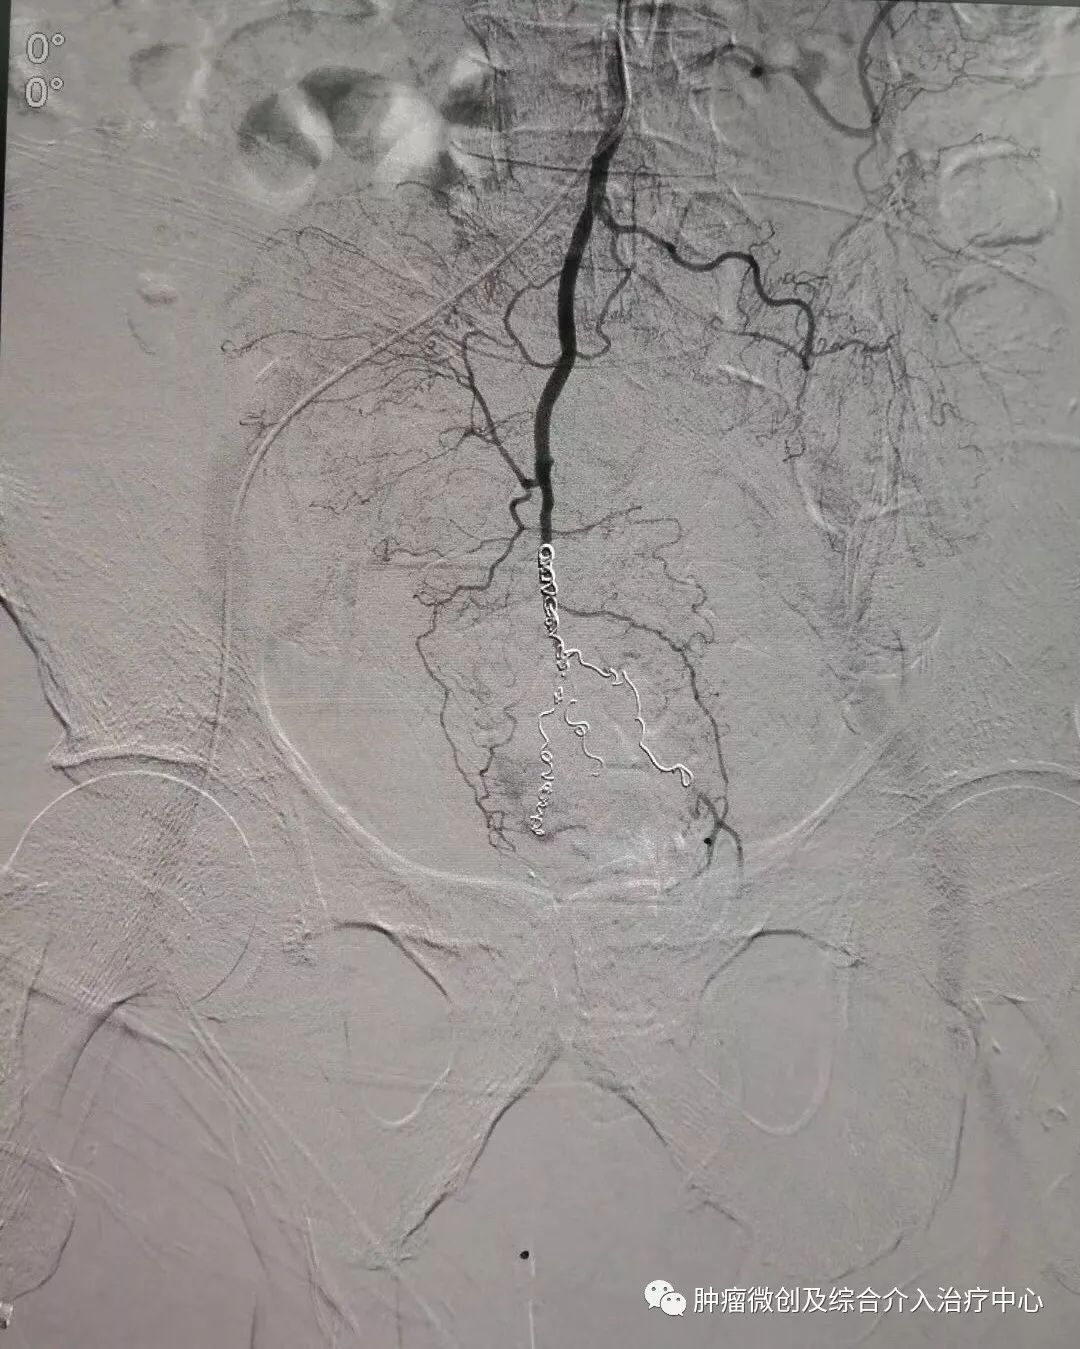

(鼻咽癌颈部转移瘤破溃出血,DSA造影提示左颈部病变血管迂曲、紊乱,内有出血)

(介入栓塞病变血管后,DSA示肿瘤病变血管栓塞好,血管走向清晰,出血停止)项目介绍:头颈部良、恶性肿瘤临床常见,其良性见于鼻咽纤维血管瘤,恶性者见于鼻咽、鼻窦癌,颈部转移性肿瘤等; 传统止血治疗疗效有限,给患者及家属带来极大的精神压力,介入手术栓塞病变血管可达到确切的止血效果,并致病变缺血萎缩。04急性肺栓塞介入手术治疗